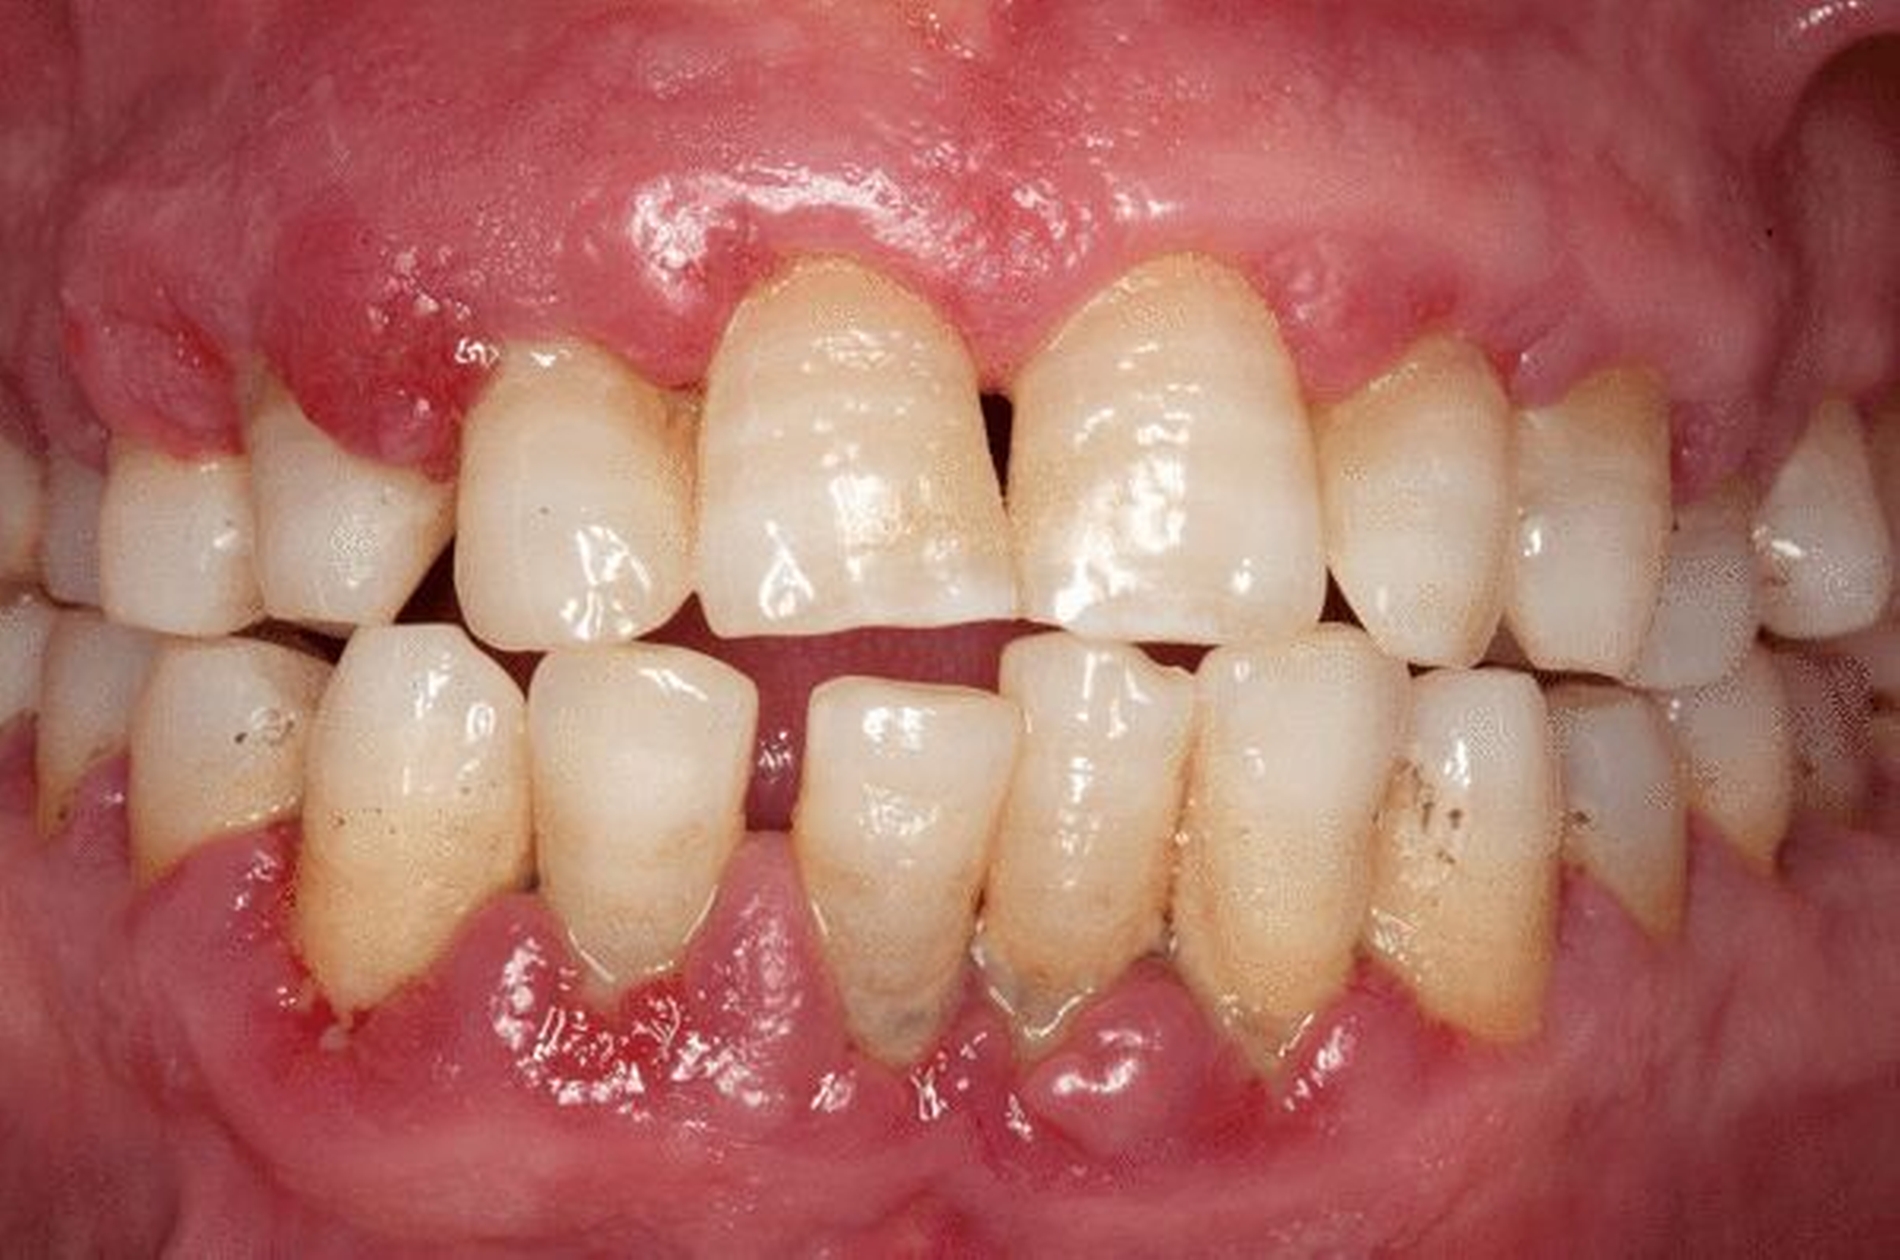

Trotz unterschiedlicher Erkrankungsbilder teilen Karies und Parodontitis eine Reihe gemeinsamer Risikofaktoren. Im Mittelpunkt stehen dabei die Prozesse im oralen Mikrobiom und die damit verbundenen Einflüsse und Wechselwirkungen in und mit den hier vorhandenen Biofilmen. Die Entstehung und das Fortschreiten beider Erkrankungen ist gekoppelt an Plaqueakkumulation und Veränderungen in den mikrobiellen Wechselwirkungen.